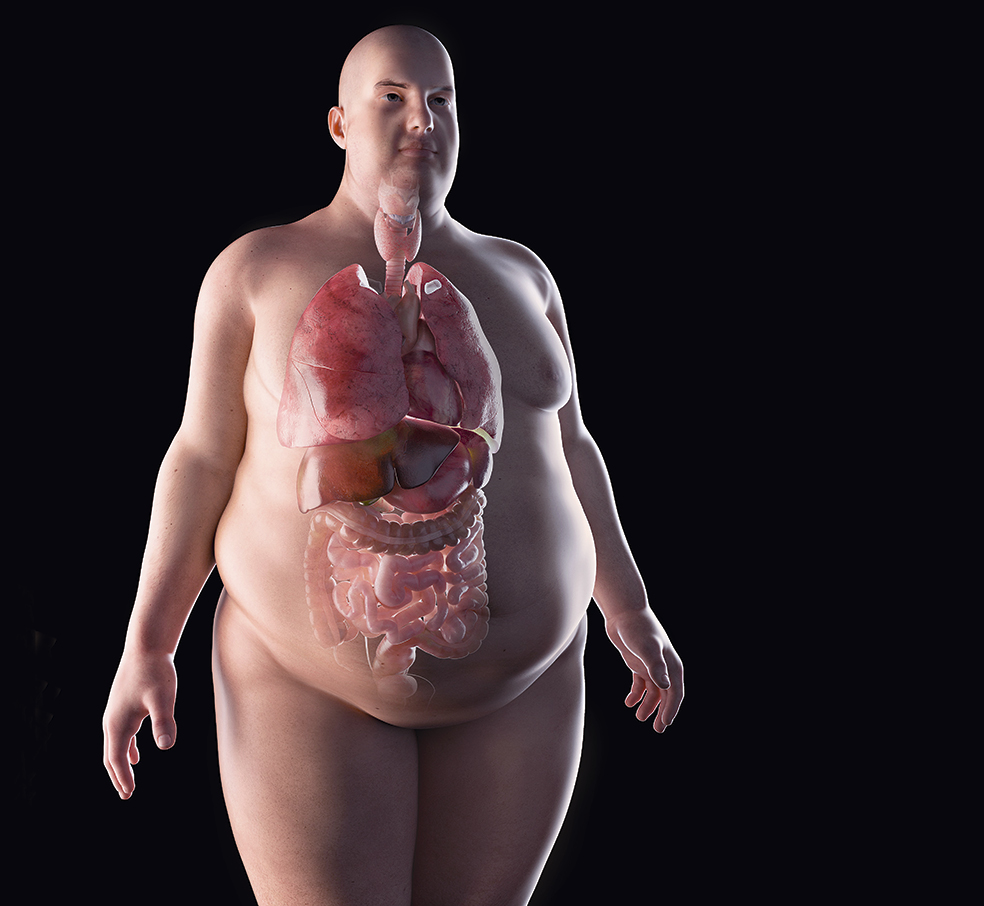

Plásticos y tóxicos

En este sentido, la doctora Navarro corrobora que «están aumentando las enfermedades autoinmunes, pero no sabemos la causa concreta. En los últimos años se está hablando mucho de los contaminantes ambientales, los plásticos… Suponemos que es la acumulación de todo, pero no hay una relación causa-efecto demostrada».

Quien tiene pocas dudas de la repercusión de los contaminantes ambientales es el doctor Olea: «Hay una hipótesis que cobra fuerza, la de que estos compuestos tóxicos interfieren en la función tiroidea o en los niveles de hormonas circulantes. Por decirlo de una manera simple, las enzimas encargadas de transformar la hormona T4 en T3 están demasiado ocupadas metabolizando contaminantes, limpiando, y no se ocupan de su función».

Desde esta perspectiva, la enfermedad no estaría tanto en el tiroides como en todo el 'ruido' alrededor. «Es una hipótesis factible que encaja en las fechas: el incremento de enfermedades tiroideas coincide con el aumento a la exposición a contaminantes bromados».

Es posible, pero no está probado. Igual que tampoco tenemos explicación que justifique la predilección de las enfermedades tiroideas por la mujer. Según David Vargas, «también hay una epidemia de niveles elevados de estrógenos en la mayoría de las mujeres, que provocan inflamación y predisponen a patologías autoinmunes».